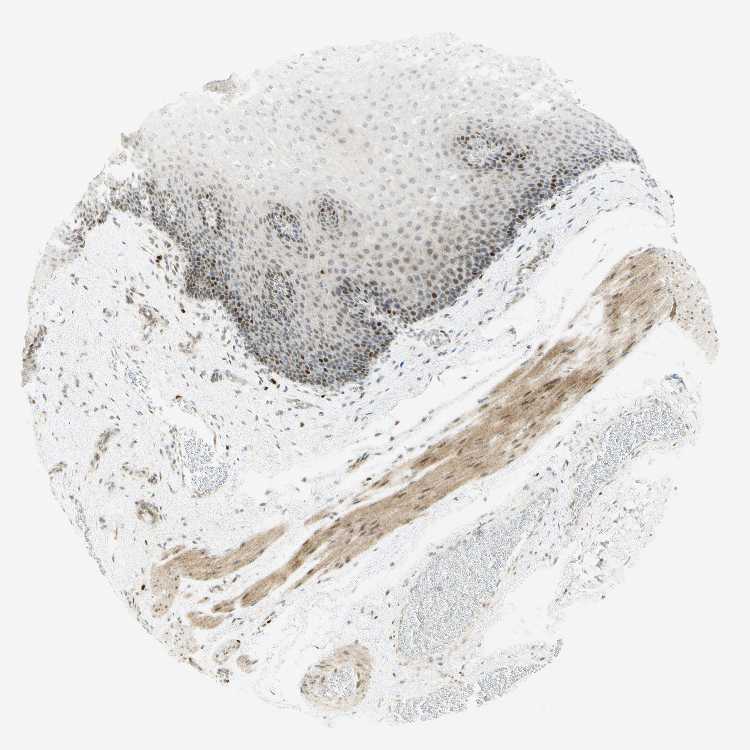

ESOPHAGUS - Antibody stainingi

Antibody staining in the annotated cell types in the current human tissue is reported as not detected, low, medium, or high, based on conventional immunohistochemistry profiling in selected tissues. This score is based on the combination of the staining intensity and fraction of stained cells.

Each image is clickable and will lead to virtual microscopy that enables deeper exploration of all samples and also displays staining intensity scores, fraction scores and subcellular localization as well as patient and tissue information for each sample.

Antibody HPA008003Antibody CAB000329Antibody CAB019308

Squamous epithelial cells HighMediumHigh